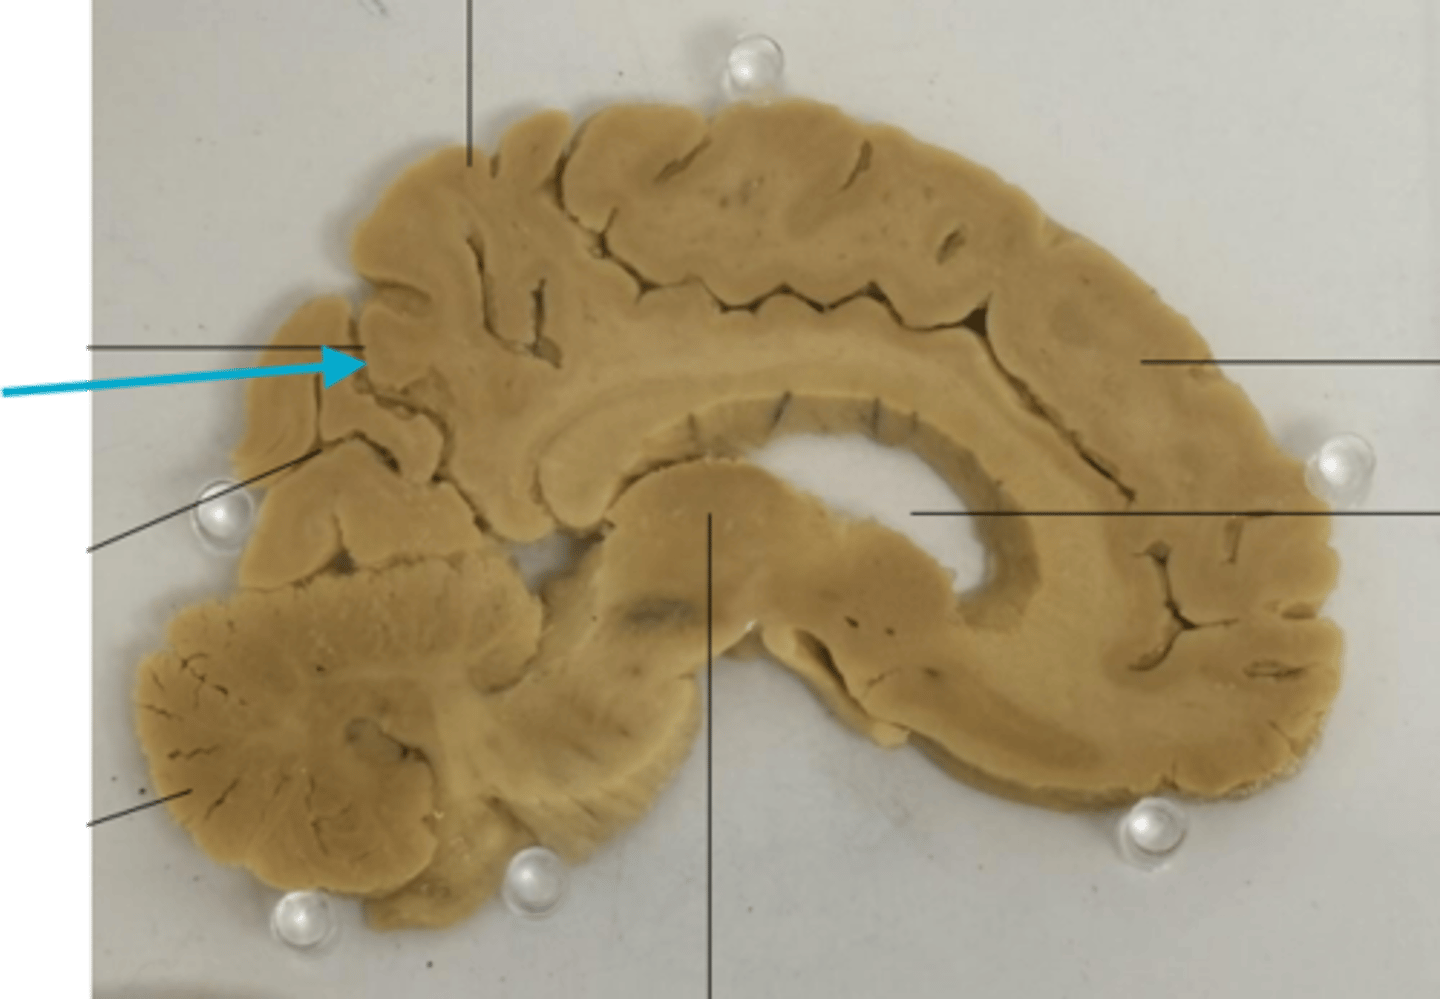

What is the blue arrow pointing at?

What number is the post central gyrus?

what is the blue arrow pointing to?

blue arrow is pointing to which structure?

The area the blue arrow is pointing to?

What area is the blue arrow pointing to?